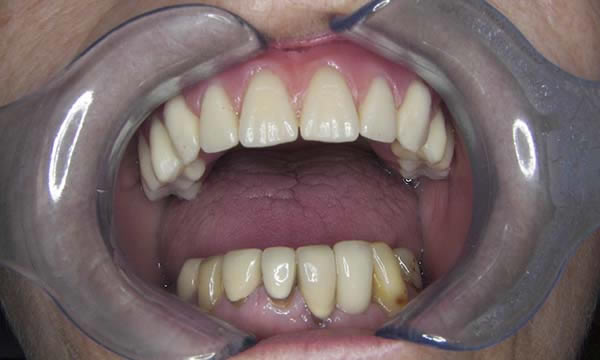

This lady had a very comfortable but loose denture that she had been using for many years. With the loss of her UR5 she decided to close the space and incorporate it into a new implant retained denture. She also decided to replace her lost LL2 with an implant retained crown.

The Kerator overdenture attachment system was used to provide predictable and stable retention for her maxillary denture and the single implant retained crown closed the lower anterior space well. Restoring both form, maxillary lip support, function and confidence.